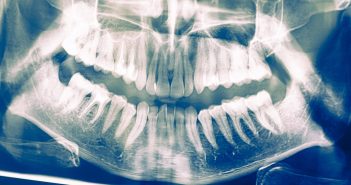

Hier stimmt etwas nicht. Betroffenen ist das meist sofort klar. Sie haben eine ruckartige Bewegung…